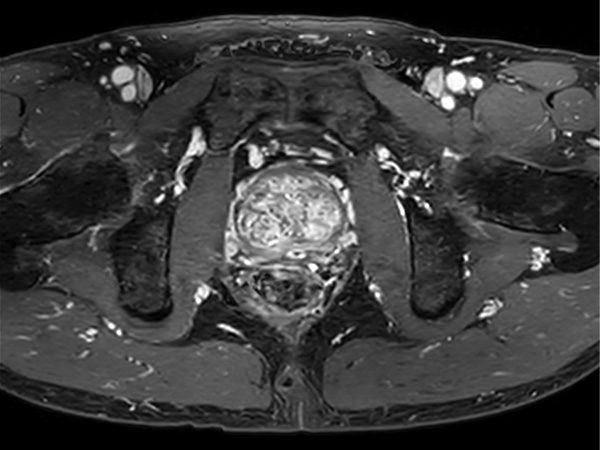

Fast Prostate imaging with SmartSpeed Precise

Kumamoto Chuo Hospital Japan

Used Solution